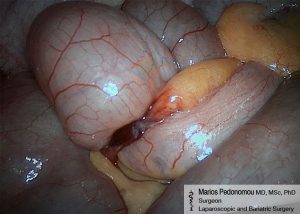

Εκκόλπωμα Meckel

Το εκκόλπωμα Meckel μοιάζει με μικρό σακουλάκι πάνω στο τοίχωμα του λεπτού εντέρου. Εμφανίζεται στο 2% περίπου των ανθρώπων και είναι συνήθως ασυμπτωματικό. Μπορεί να φιλοξενεί έκτοπο ιστό και να προκαλέσει αντίστοιχη επιπλοκή. Μπορεί να αιμορραγήσει, να πάθει συστροφή (να περιστραφεί δηλαδή γύρω από τον άξονα του και να νεκρωθεί), εγκωλεασμό, φλεγμονή (εκκολπωματίτιδα), ακόμη και καρκίνο. Στην περίπτωση που το εκκόλπωμα γίνει συμπτωματικό, τότε θα πρέπει να αφαιρεθεί. Η θεραπεία του είναι η χειρουργική του αφαίρεση και αυτή μπορεί να γίνει με λαπαροσκοπική χειρουργική.